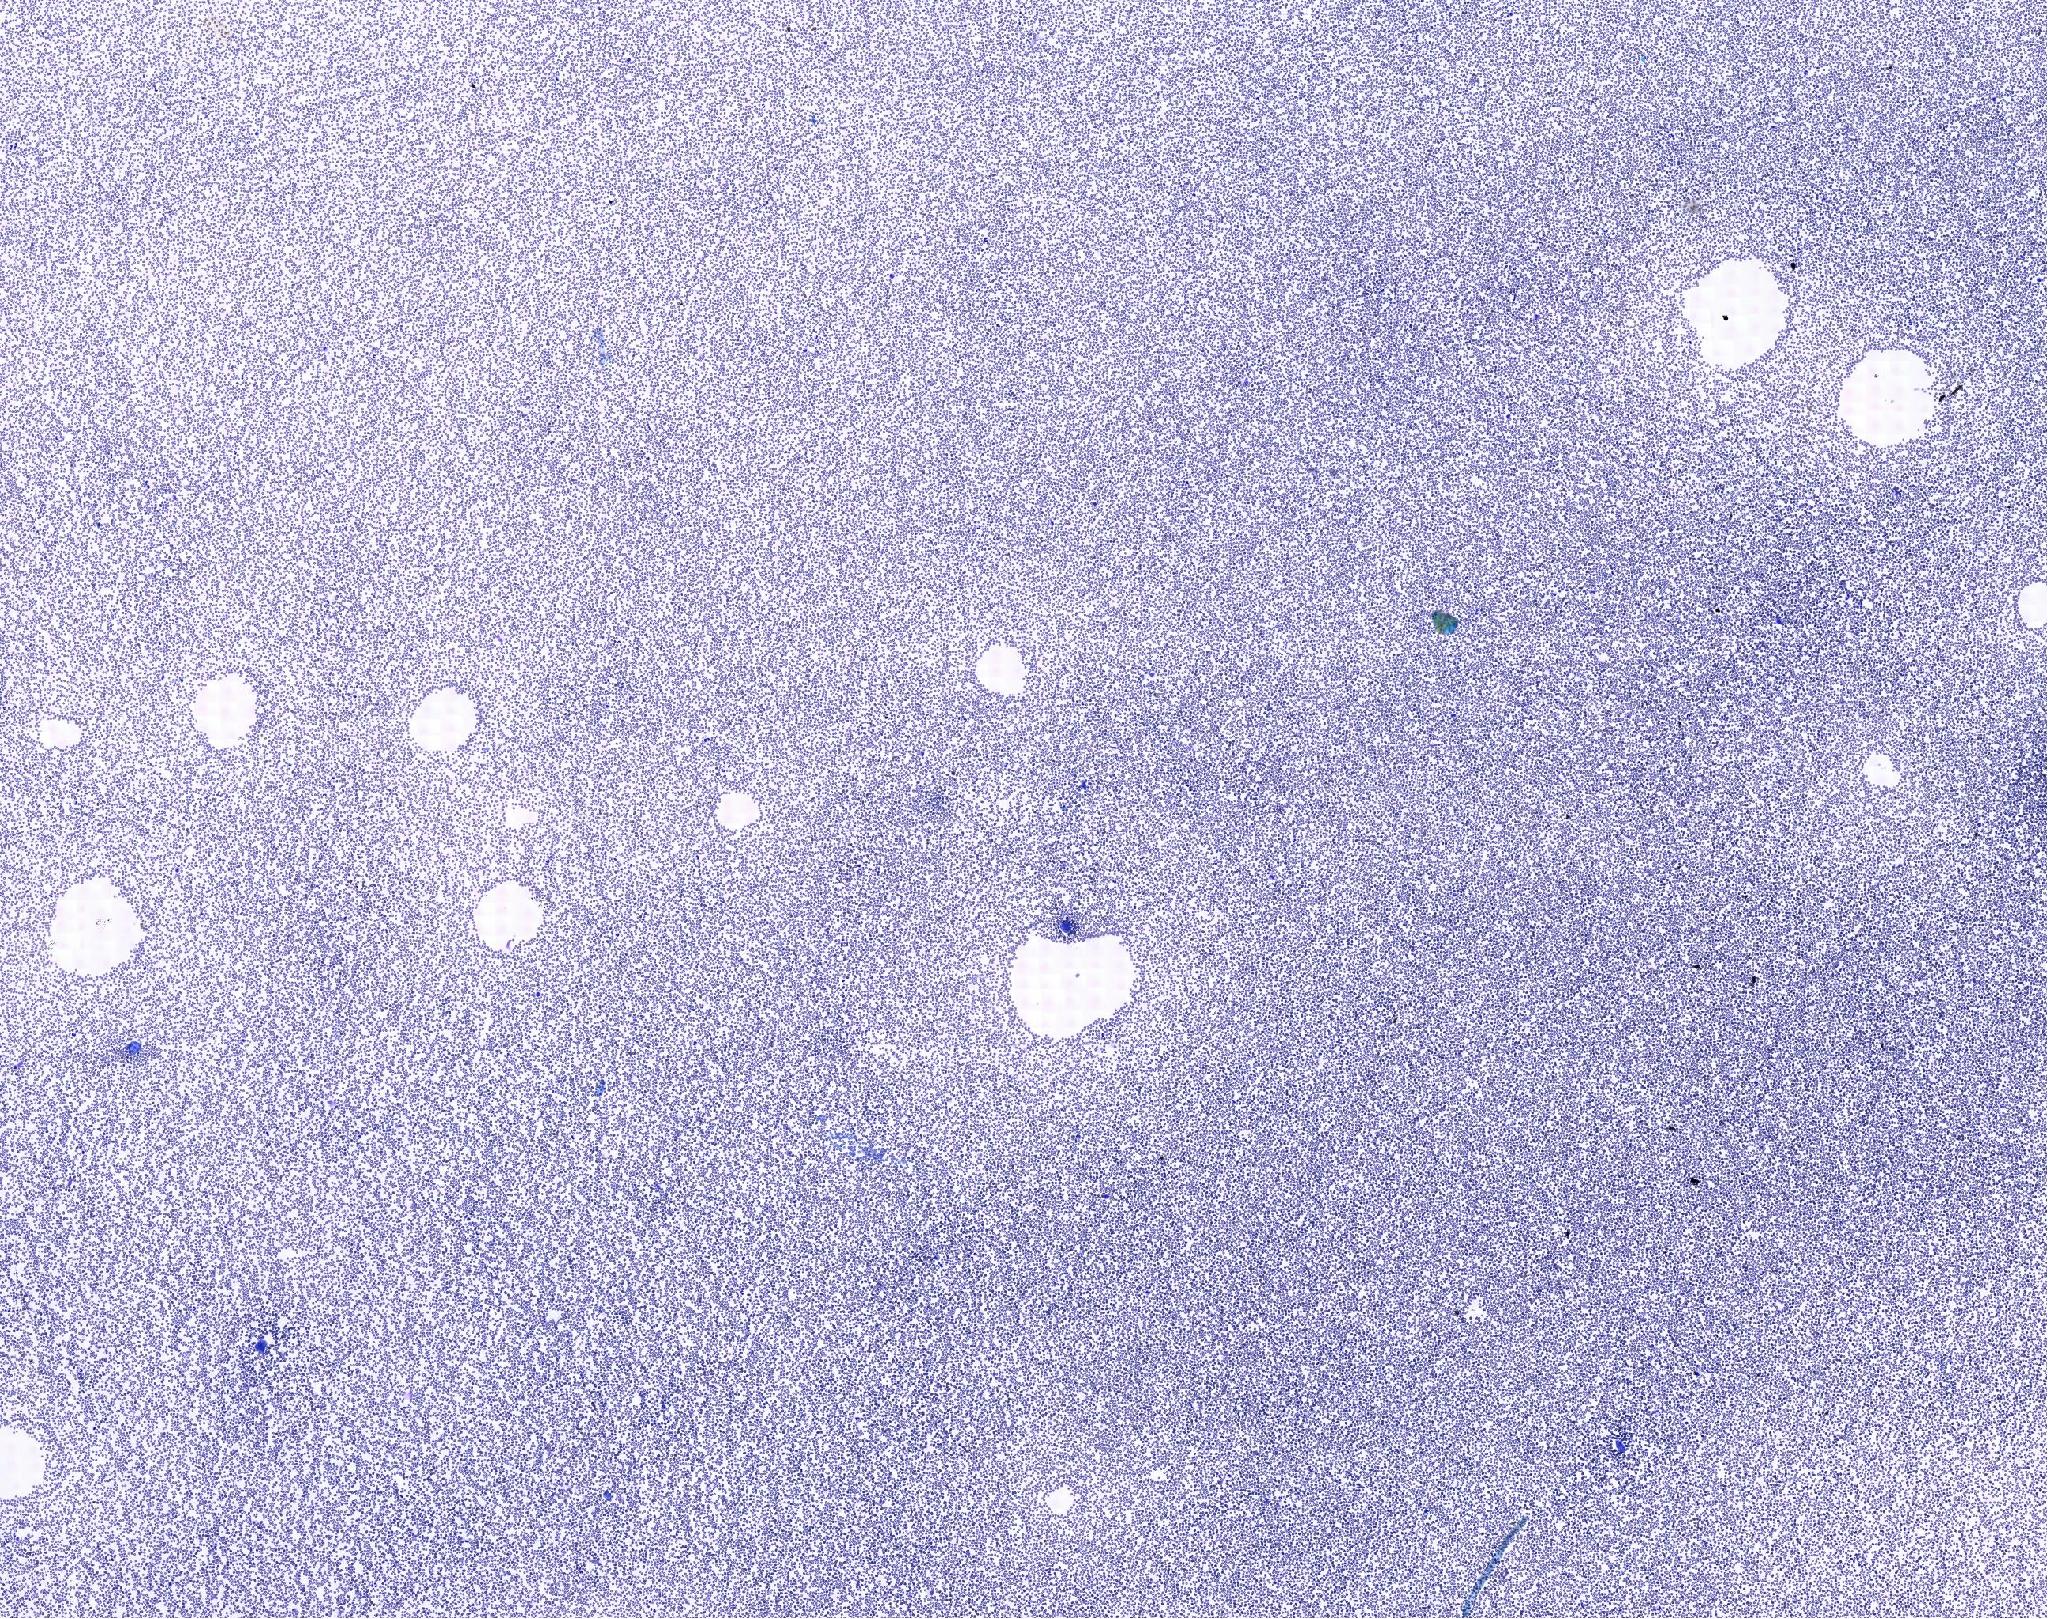

Normal bone marrow 11521041658_5152

골수 / 정상 / 개

Normal canine Sample: bone marrow aspiration(골수흡인표본)